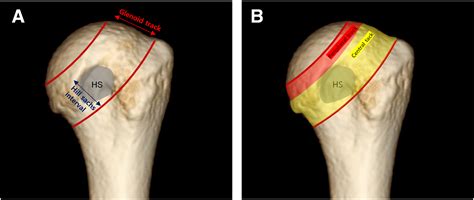

A Hills Sachs lesion is a specific type of injury that occurs in the shoulder joint, typically following an anterior shoulder dislocation. It is defined as an impaction fracture on the posterolateral aspect of the humeral head—the "ball" part of the shoulder joint. When the shoulder pops out of its socket, the soft, rounded bone of the humerus is forced against the sharp, hard edge of the glenoid (the socket), resulting in a depression or indentation in the bone. Understanding the nature of this injury is crucial for anyone involved in sports, physical therapy, or orthopedic recovery, as it directly impacts the long-term stability and function of the shoulder joint.

The shoulder is a ball-and-socket joint, designed for a vast range of motion. However, this flexibility comes at the cost of stability. When an anterior shoulder dislocation occurs, the humeral head is pushed forward and out of the socket. In many cases, the bone travels until it strikes the glenoid rim. Because the bone of the humeral head is relatively soft, the harder bone of the glenoid rim acts like a stamp, creating a “divot” or notch in the humeral head.

This indentation is the Hills Sachs lesion. It is important to note that these lesions are highly prevalent in patients who experience recurrent shoulder instability. Once the bone has been dented, the "locking" mechanism of the shoulder is compromised, making it easier for the joint to dislocate again in the future. This creates a cycle of instability that often requires medical intervention to correct.